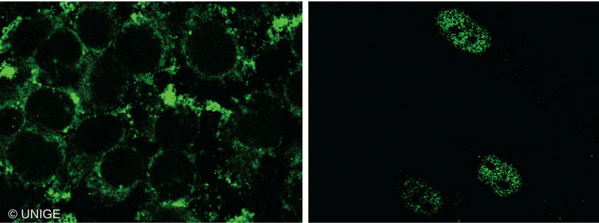

双靶点成功治疗多发性骨髓瘤

记者6月21日获悉���,南京传奇生物科技有限公司与西安交通大学第二附属医院合作展开的多靶点CAR-T疗法临床试验表现出惊人的客观缓解率,在近日举行的美国临床癌症学会年会上��,该疗法引起与会专家的高度评价和瞩目�。“患病后��,人体免疫细胞无法识别肿瘤细胞��,导致肿瘤快速复制转移病情扩散”���,南京传奇生物科技有限公司首席科学家兼创始人范晓虎说����,这种CAR-T疗法的特点是双靶点治疗,“目前大多数CAR-T疗法是一个靶点����,就像用一只手去抓球极易脱手,而双靶点相当于两只手去抓球����,成功率大大增加”。多发性骨髓瘤是三大血液系统恶性肿